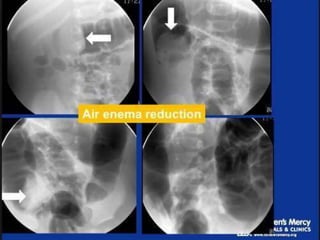

Air is insufilated into the colon

under fluoroscopic observation

Reduction is followed fluoroscopically

until it is completely reduced

Air should flow freely from the cecum into the

distal small bowel loops to signify complete

reduction

Keep air pressure below a maximum limit

of 120 mm Hg to avoid the risk of

perforation

The enema tipshould be placed within the child’s rectum and taped securely in place Child is placed in a prone position to squeeze the buttocks closed and prevent air from leaking Air is insufilated into the colon under fluoroscopic observation Reduction is followed fluoroscopically until it is completely reduced

• 48.

Air should flowfreely from the cecum into the distal small bowel loops to signify complete reduction Keep air pressure below a maximum limit of 120 mm Hg to avoid the risk of perforation